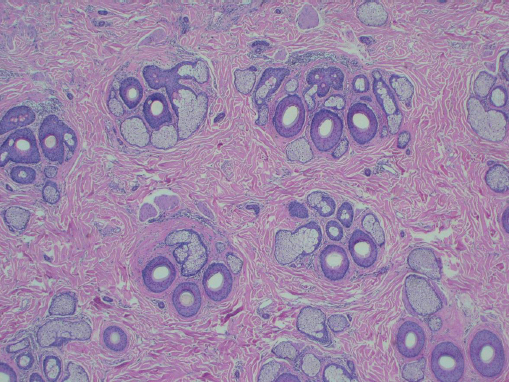

Hair follicles of the scalp naturally exist as follicular units ( Fig. 28.2 ). The follicular unit consists of one to four terminal hairs with or without several vellus hairs, a sebaceous gland and duct, arrector pili muscle, and a common vascular and neural plexus. The entire unit is surrounded by a connective tissue sheath. Using microscopy, the structure of the follicular unit and the surrounding area of non–hairbearing skin is visible ( Fig. 28.3 ).

In scarring alopecia, inflammation occurs in the upper part of hair follicle leading to destruction of stem cells and the associated sebaceous gland. As a result, the hair follicle is replaced with scar tissue causing permanent hair loss. Clinically, affected areas lack hair, have smooth skin, and have no normal pore structures. In the active phase, erythematous and scaly skin is present at the periphery of the affected area. Diagnosis is achieved with a punch biopsy. Caution must be taken when proceeding with hair transplantation in patients with scarring alopecias. In active disease, grafts are unlikely to be successful and the disease can reactivate at any time resulting in graft loss. Test grafts, alopecia reduction procedures, an observation period prior to procedures, and a longer waiting period between sessions should also be considered. Scarring alopecia includes a spectrum of diseases: lichen planopilaris, central centrifugal alopecia, discoid lupus, pseudopelade (Brocq), folliculitis decalvans, tufted folliculitis, dissecting cellulitis, linear scleroderma, sarcoidosis, and frontal fibrosing alopecia.